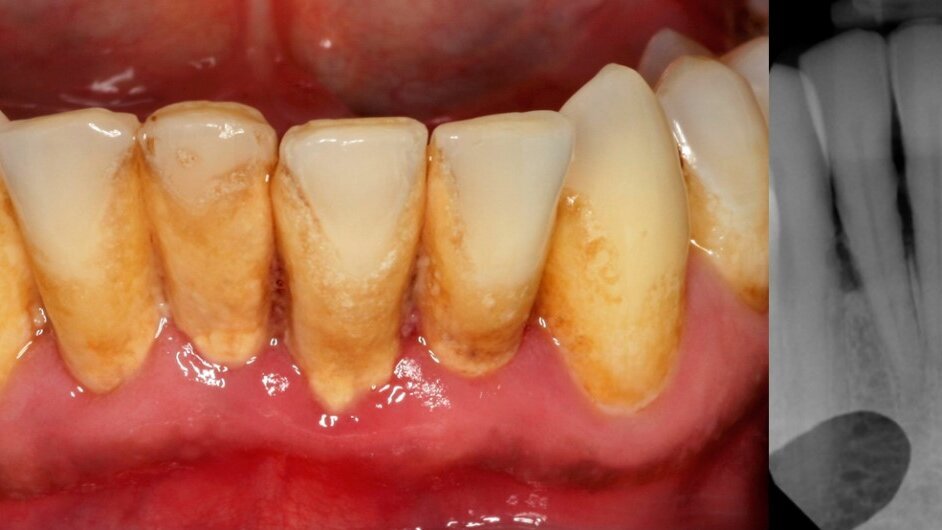

SENDAI, Japan: Periodontitis is a common oral disease that affects the oral health of many people with serious effects. A new research from Japan proposes a novel cell-based regenerative approach, which promises to address & overcome some of the shortcomings and limitations of the regenerative therapies, currently being used for the treatment of periodontitis.

Various treatment approaches, such as guided tissue regeneration (GTR), platelet-rich plasma (PRP), and enamel matrix derivatives (EMD), have been in use for long with success rates that are variable in their ability to regenerate the lost periodontal tissues. A variety of recombinant human cytokines too have been investigated for their ability to stimulate the regeneration of periodontal tissues. However, the above-mentioned regenerative therapies have shown predictable outcomes only in the three- wall periodontal defects. They still remain unpredictable in advanced periodontal defects, where the resident progenitor cells are reduced or destroyed.